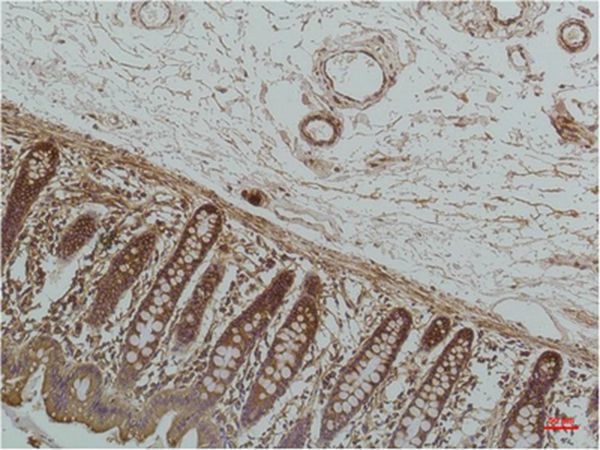

Immunohistochemical analysis of paraffin-embedded Human Colon Caricnoma using GRP78/BipMouse mAb diluted at 1:200.